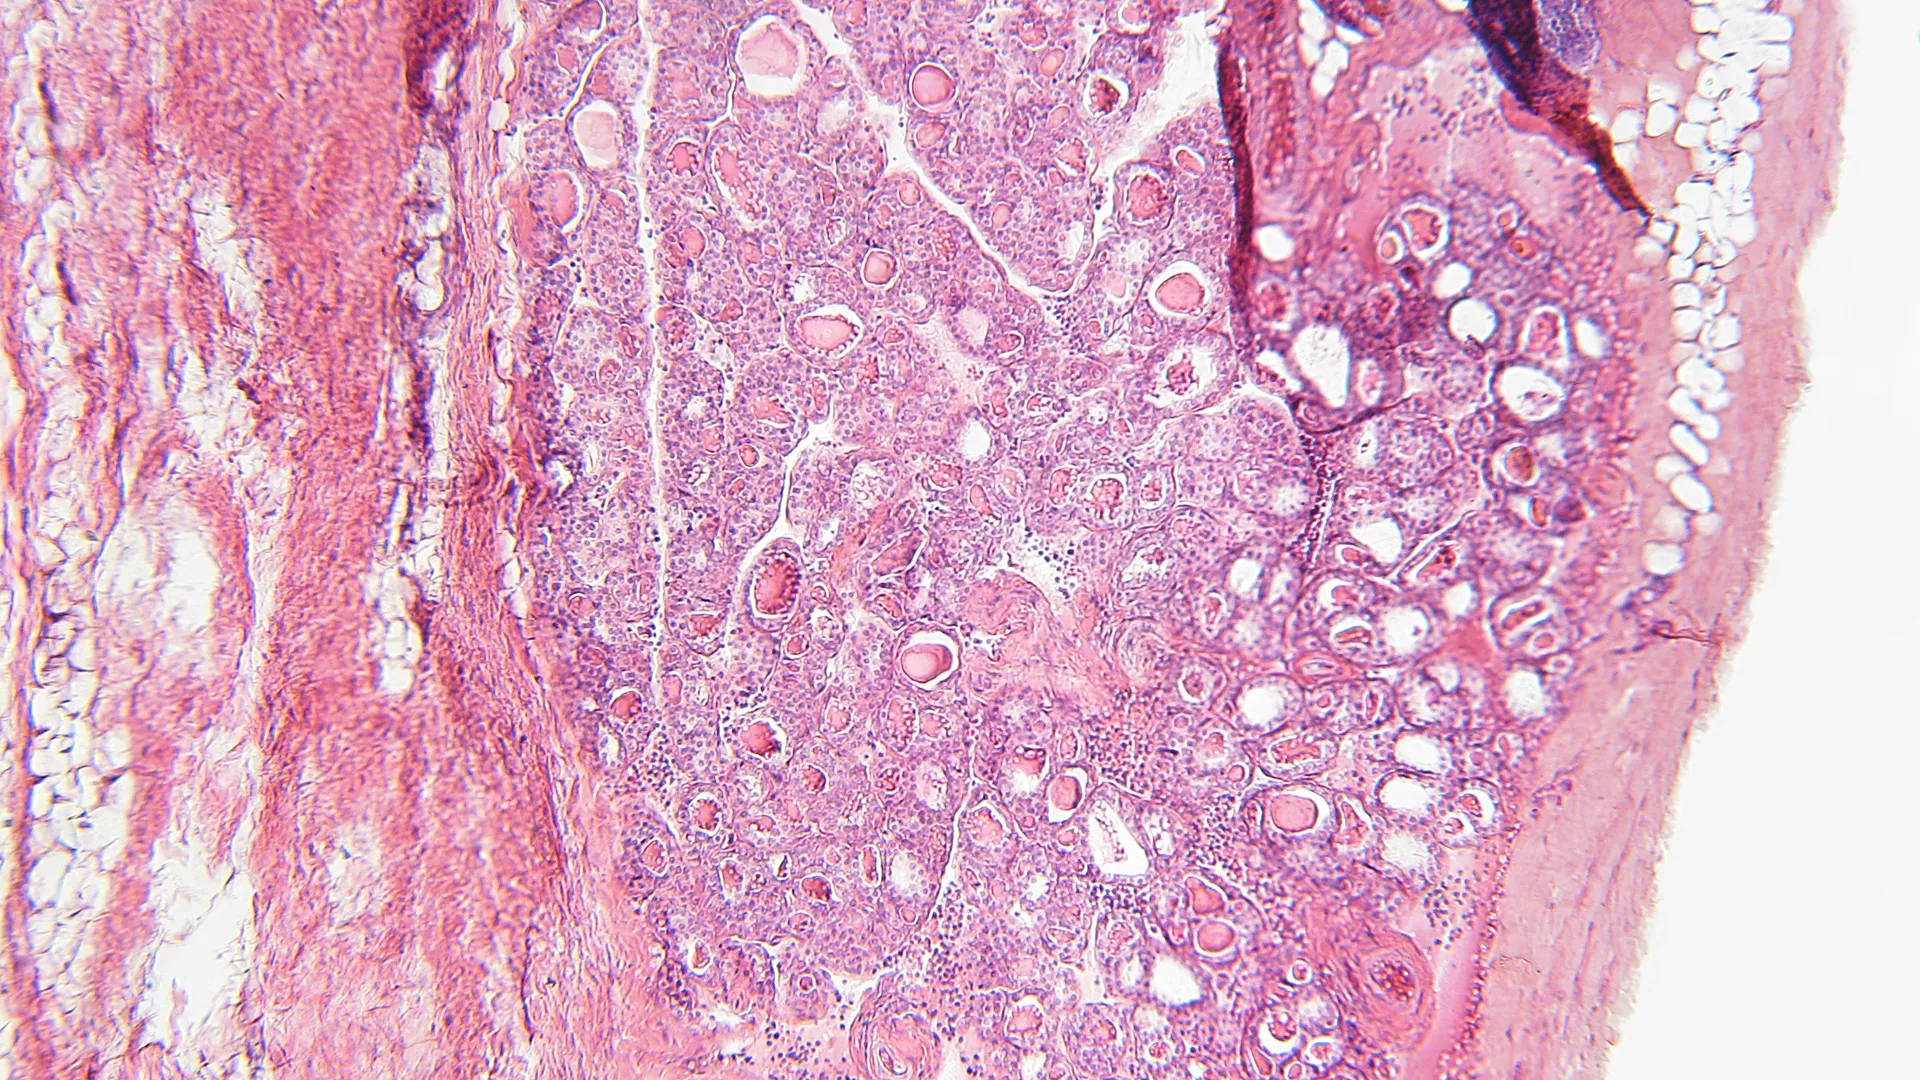

Een 46-jarige Braziliaanse man werd verwezen naar nefrologie wegens stijgend creatinine. Hij werd gevolgd door longartsen voor een interstitieel longbeeld. Hist